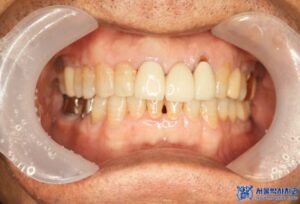

오늘은 오래전에 하악 어금니를 발치하고

그 상태로 지내시다가,

전체적으로 치료를 받으러 오신 환자분의

임플란트 치료 및 신경 치료 사례를

소개해 드리도록 하겠습니다.

위 환자분께서는 오랫동안 없던 어금니뿐만 아니라

나머지 불편한 치아들도 함께 치료를 원하셨는데요.

신경치료가 끝난 어금니는 치아를 보호하기 위해

크라운 치료를 진행하였습니다.

추가적으로, 충치 범위가 크지 않은 송곳니와

작은 어금니는 레진 치료를 진행하였습니다.

환자분은 전체적인 치료를 마친 후,

전체적으로 치아가 건강해진

느낌이 든다고 말씀하셨습니다.